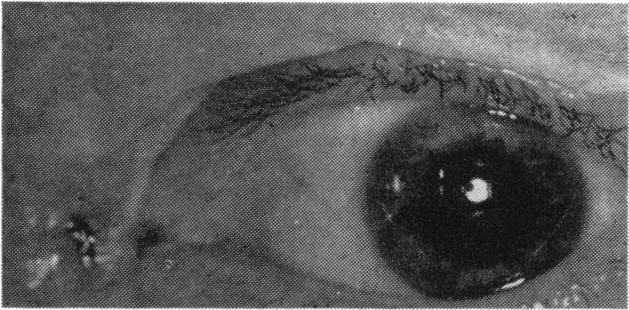

Beta radiation therapy in ophthalmology.

https://cdn.ncbi.nlm.nih.gov/pmc/blobs/bc37/1313186/f131e5c35426/taos00049-0488-a.jpg